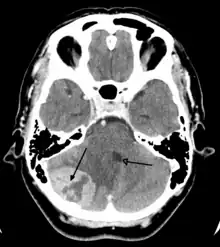

Imaging

Medical imaging plays a central role in the diagnosis of brain tumors. Early imaging methods – invasive and sometimes dangerous – such as pneumoencephalography and cerebral angiography have been abandoned in favor of non-invasive, high-resolution techniques, especially magnetic resonance imaging (MRI) and computed tomography (CT) scans,[38] though MRI is typically the reference standard used.[41] Neoplasms will often show as differently colored masses (also referred to as processes) in CT or MRI results.

- Benign brain tumors often show up as hypodense (darker than brain tissue) mass lesions on CT scans. On MRI, they appear either hypodense or isointense (same intensity as brain tissue) on T1-weighted scans, or hyperintense (brighter than brain tissue) on T2-weighted MRI, although the appearance is variable.

- Contrast agent uptake, sometimes in characteristic patterns, can be demonstrated on either CT or MRI scans in most malignant primary and metastatic brain tumors.

- Pressure areas where the brain tissue has been compressed by a tumor also appear hyperintense on T2-weighted scans and might indicate the presence of a diffuse neoplasm due to an unclear outline. Swelling around the tumor known as peritumoral edema can also show a similar result. This is because these tumors disrupt the normal functioning of the BBB and lead to an increase in its permeability.